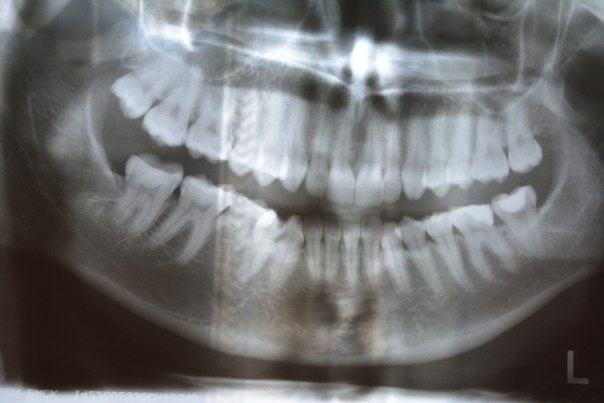

Здравствуйте! Около 5-ти лет назад мне удалили зуб мудрости. Процедура происходила следующим образом: разрезали десну, затем — разбивали зуб, вытащили его (он был нецелый), взяли с вены кровь, поставили ее в какой-то аппарат, чтобы она стала сгустком, положили этот сгусток на место зуба и зашили. Дело в том, что зуб рос неправильно, под наклоном, поэтому его пришлось удалять до того, как он прорезался. А кровь положили на его место, как мне объяснил стоматолог, для того, чтобы зажило быстрее и без проблем. У меня поднялась температура до 37,2, держалась больше месяца, я обратилась к стоматологу, он сказал, что всё в порядке и её причины не понимает. Я решила обратиться к терапевту: сдала общие анализы и посев крови, врач ничего не обнаружил. На этом хождения по врачам закончились, а температура держится уже 5 лет, но она не постоянно 37,2, может быть больше или немного меньше. Поначалу смерилась с тем, что ну может изменилась терморегуляция. Но спустя 3 года начала очень часто болеть, каждый месяц (тонзиллит, фарингит, ларингит). Мог ли врач занести какой-то вирус, бактерии, которые так ослабили иммунитет и так влияют на горло? Лор-врачи на тонзиллэктомию пока не решаются. Может мне нужно сдать дополнительные анализы? Само место (десна) после удаления зуба не тревожит абсолютно, покраснения нет. На данный момент никакие зубы не беспокоят, единственно, что на зубах камни. Недавно сдавала анализы на ВИЧ и СПИД, результаты отрицательные. Во вложении снимок челюсти, возможно, он чем-то поможет. Описанную процедуру удаления проводили с левой стороны. С правой стороны, под которой написана английская буква L, тоже удаляли, но самым обычным методом, после которого вообще не было температуры. Заранее благодарна за ответ!

Если честно, не вижу смысла в данной процедуре (кровь , центрифуга и так далее), это совершенно не тот случай, банальное удаление восьмого, даже самого сложного зуба не требует данной процедуры в обязательном порядке. Действия доктора правильные и по снимку не вижу патологий. Постоянная температура никак не связана с удалением, но этот не норма. Рекомендую пройти комплексное обследование (легкие , щитовитку и так далее) на предмет воспаления. Постоянная температура говорит о хроническом воспалительном процессе.